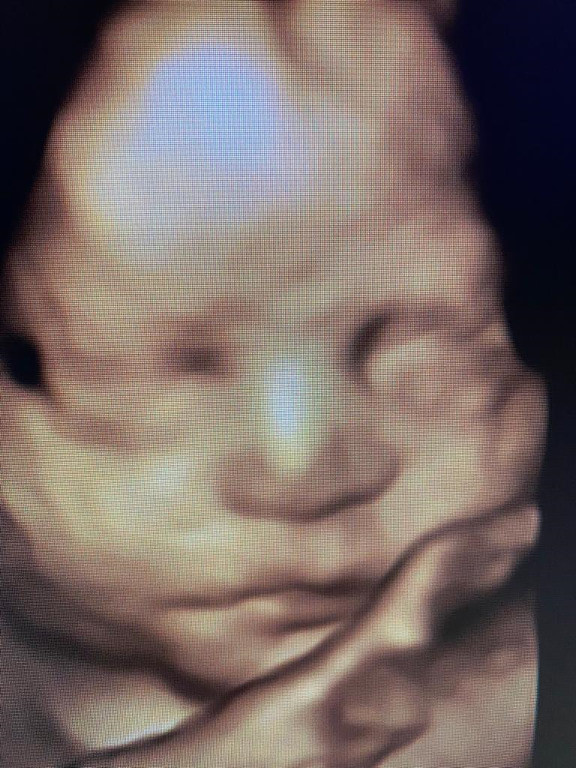

Atención de parto

Envíado por Dra. Erika Lissette Palacios